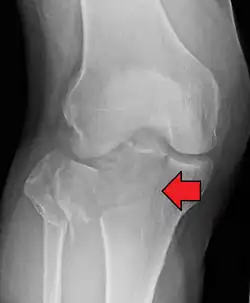

A severe tibial plateau fracture with an associated fibular head fracture

A tibial plateau fracture is a break of the upper part of the tibia (shinbone) that involves the knee joint.[1] This could involve the medial, lateral, central, or bicondylar (medial and lateral).[3] Symptoms include pain, swelling, and a decreased ability to move the knee.[1] People are generally unable to walk.[2] Complication may include injury to the artery or nerve, arthritis, and compartment syndrome.[1]

Fractures of the tibial plateau are caused by a varus (inwardly angulating) or valgus (outwardly angulating) force combined with axial loading or weight bearing on knee. The classically described situation in which this occurs is from a car striking a pedestrian's fixed knee (bumper fracture). A bumper fracture is usually a fracture of the lateral tibial plateau, caused by a forced valgus movement. This causes the lateral part of the distal femur and the lateral tibial plateau to come into contact, compressing the tibial plateau and causing the tibia to fracture. The name of the injury is because it was described as being caused by the impact of a car bumper on the lateral side of the knee while the foot is planted on the ground, although this mechanism is only seen in about 25% of tibial plateau fractures.[5] The term "bumper fracture" was coined in 1929 by Cotton and Berg.[6] Fracture of the neck of the fibula may also be found, and associated injury to the medial collateral ligament or cruciate ligaments occurs in about 10% of cases.[7][8]